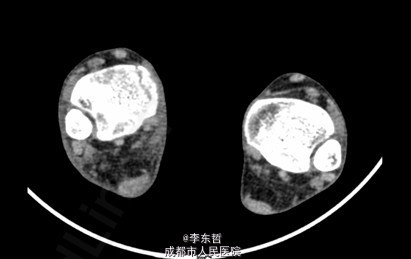

患者女,13岁4月,因“车祸致右足跟部皮肤撕脱伤清创缝合术后25天”入院。患者25天前因车祸导致右足疼痛流血伴功能障碍,右足跟部皮肤撕脱,遂到当地医院就诊,诊断为右足跟部皮肤严重剥脱伤,右跟骨骨折,右胫骨远端骨折。急诊下行“右足跟部皮肤严重剥脱伤清创缝合术”。术后给予止痛、消肿、预防感染等对症处理,目前右足外侧及跟部皮肤变暗,坏死。患者为进一步诊疗,故请我院远程会诊后转入我科继续治疗。患者病来精神、饮食可,大小便正常,体重未见明显改变。

查体:右足内踝、外踝及跟部皮肤变暗,部分缺血坏死。未见畸形,稍肿胀。触:右足趾皮温无明显降低,右足趾感觉未见明显异常。右足内踝、外踝及跟部皮肤局部压痛。动量:右踝关节活动受限,右踝关节活动诱发疼痛。右膝关节活动未见明显异常。 辅助检查:X线示:右跟骨骨折,右胫骨远端骨折。

初步诊断:1、右足跟部皮肤软组织撕脱伤清创缝合术后皮肤软组织大面积坏死伴感染;2、右跟骨骨折;3、右胫骨远端骨折;4、右足跖屈畸形。 处理:1、向患者及家属交待病情及注意事项。2、向上级医生汇报患者病情。3、完善相关术前等检查,择期行手术治疗。4、给予对症支持治疗。5、密切观察病情变化,根据病情及时处理。